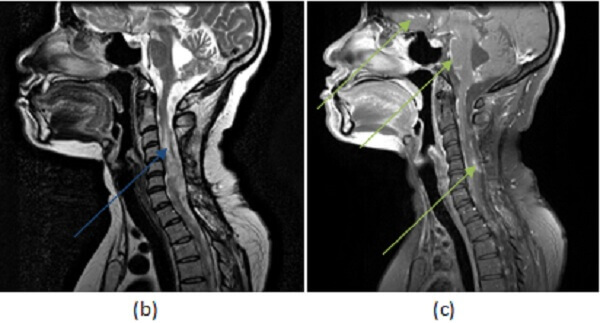

Figure 1: (a, red arrow) axial postcontrast T1 demonstrates enhancement of the leptomeningeal surface along the basal cisterns. (b, blue arrow) Sagittal T2 of the spine demonstrates increased T2 signal involving an expanded cervical cord. (c, green arrow) Sagittal T1 post contrast of the spine and brain demonstrates intramedullary and leptomeningeal enhancement of the cervical cord, along with parasellar, frontal and cerebellar leptomeningeal enhancement.

The cord is involved in about 25% of neurosarcoid cases – leptomeningeal and intraparenchymal enhancement are the most common findings. There is no disease modifying therapy for sarcoidosis yet available. Corticosteroids are helpful in reducing the extent of inflammation.

Leptomeningeal (pial and arachnoid) involvement with perimedullary enhancement is most common, with preferential involvement of the parasellar region and the cranial nerves, especially the optic chiasm. Predilection for these spaces can help distinguish sarcoid from other causes of leptomeningeal enhancement like meningitis, metastatic disease, vasculitis and subacute infarct. Enhancing intraparenchymal granulomas may also be seen in neurosarcoid. Complications include hydrocephalus and vasculitis.